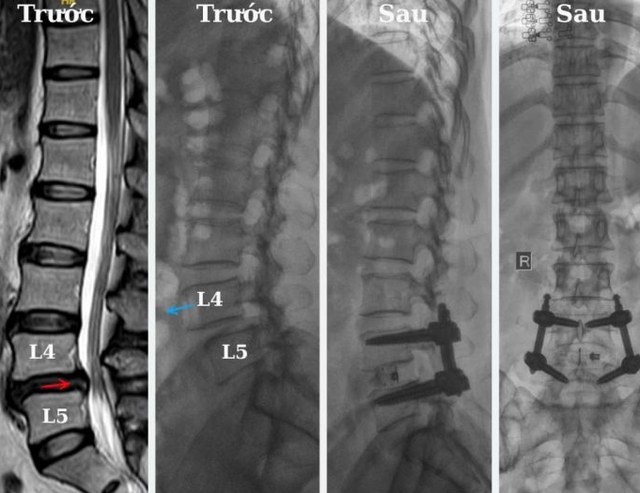

Hình ảnh cận lâm sàng trước và sau của bệnh nhân thoát vị đĩa đệm. Ảnh: BVCC

Được gia đình động viên, cô L. quyết định quay lại BVĐK Xuyên Á Tây Ninh để tái khám. Kết quả chụp MRI cho thấy bệnh đã tiến triển nặng hơn với tình trạng trượt đốt sống L4–L5 độ I, thoát vị đĩa đệm và hẹp ống sống. Sau khi được bác sĩ tư vấn kỹ lưỡng, cô đã mạnh dạn đồng ý thực hiện phẫu thuật.

Ca mổ do BS.CKI. Hồ Hoài Hưng – Trưởng khoa Ngoại Thần Kinh trực tiếp thực hiện cùng ê-kíp phẫu thuật, áp dụng kỹ thuật nắn trượt hàn xương liên thân sống qua nội soi – một phương pháp hiện đại, ít xâm lấn, giúp giảm đau sau mổ và rút ngắn thời gian hồi phục.